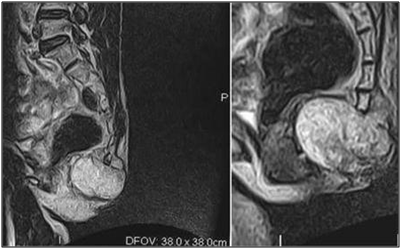

A 54 year-old male presented to the surgical out-patient department. He complained of lower backache and swelling in the gluteal region since many years. The swelling had gradually progressed to the present size. There was a recent rapid increase in size of swelling, accompanied by formation of a discharging sinus of three months duration. On examination, a 5 X 4 cm mass was present in the intergluteal fold, the overlying skin showed a discharging sinus measuring 1 X 1 cm (Figure 1). Clinical diagnosis of Pilonidal sinus was made. Routine investigations were within normal limits. The patient was referred for fine needle aspiration cytology. The smears showed abundant myxoid stroma with singly dispersed small, round cells with bland nucleus along with cells having abundant vacuolated bubbly cytoplasm and small nucleus (Figure 2). A diagnosis of myxoid rich soft tissue tumour with possibility of chordoma was suggested. Lumbar magnetic resonance imaging done subsequently revealed a well demarcated, multilobulated mass in the sacococcygeal region (Figure 3).

Figure 3 Multilobulated mass in the sacococcygeal region on Magnetic Resonance imaging.

The mass was excised and sent for histopathological examination. Gross examination showed a circumscribed soft tissue mass covered with an elliptical piece of skin with ulceration and sinus formation. Cut surface was firm to hard, vaguely lobulated and variegated with reddish brown hemorrahagic to gelatinous areas (Figure 4). Histopathology revealed a tumour composed of cells arranged in lobulated pattern separated by fibrous septa. The stroma showed myxoid areas and areas of hemorrhage and necrosis. The tumour cells were polyhedral to round with eosinophilic cytoplasm and round atypical nuclei along with physaliphorous cells. Occassional spindle shaped stellate cells and signet ring-like cells were also seen. Physaliphorous cells were large multivacoulated with bubbly appearance of cytoplasm and small inconspicuous nuclei (Figure 5). The cytoplasmic vacuoles were periodic acid Schiff (PAS) positive and diastase sensitive suggesting glycogen deposition (Figure 6). The tumour cells were seen infiltrating the capsule and surrounding soft tissue. The skin overlying tumour showed ulceration and chronic inflammatory cell infiltrate in the dermis. Diagnosis of sacrococcygeal chordoma- NOS was made.